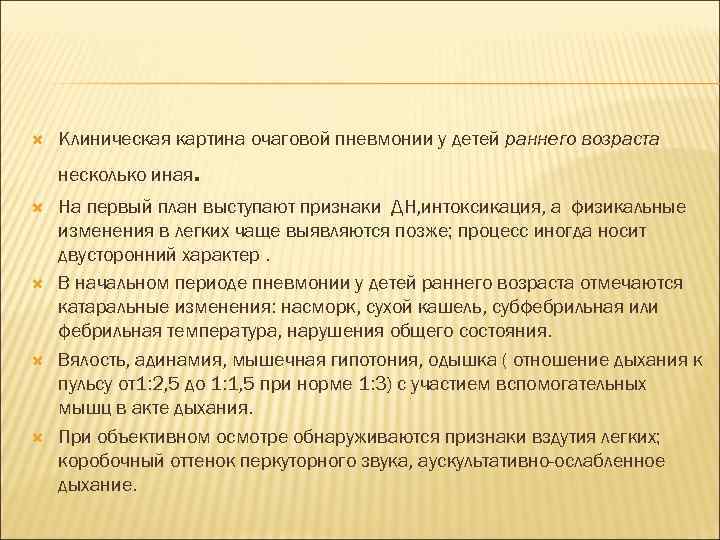

Клиническая картина очаговой пневмонии у детей раннего возраста несколько иная . На первый план выступают признаки ДН, интоксикация, а физикальные изменения в легких чаще выявляются позже; процесс иногда носит двусторонний характер. В начальном периоде пневмонии у детей раннего возраста отмечаются катаральные изменения: насморк, сухой кашель, субфебрильная или фебрильная температура, нарушения общего состояния. Вялость, адинамия, мышечная гипотония, одышка ( отношение дыхания к пульсу от1: 2, 5 до 1: 1, 5 при норме 1: 3) с участием вспомогательных мышц в акте дыхания. При объективном осмотре обнаруживаются признаки вздутия легких; коробочный оттенок перкуторного звука, аускультативно-ослабленное дыхание.